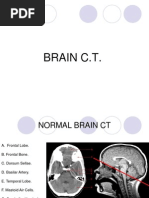

CT BRAIN

Approach to CT Brain

1. Ensure details of patient & Scan

2. Confirm orientation of scan & use of contrast

3. Systemic approach to interpreting a CT Scan:

Blood Cistern

- Circum-mesencephalic (surrounding the

- Presence of blood (origin, duration & midbrain)

cause of insult determined by location - Suprasellar (around the Circle of Willis)

& spread) - Quadrigeminal (located at the top of

- Extracerebral Hemorrhage (within the midbrain)

skull but outside of brain) - Sylvian (between temporal & frontal

lobes)

- Intracerebral Hemorrhage (within the

- Examine each cistern for evidence of

brain itself) effacement, asymmetry and presence of

blood

Ventricles

Brain

- Examine the lateral ventricles, 3rd &

- Compare the sulcal pattern (gyri) 4th ventricles

- Look for midline shift (mass effect)

(asymmetry, dilatation (hydrocephalus),

- Look for any inconsistencies in the

effacement & hemorrhage)

grey-white differentiation

- Identify hyperdense & hypodense

regions

Bones

- Look for evidence of fracture/ tumors

- Best viewed on separate bone windows

- Cortical bone has highest density on CT

- Maxillary/ Ethmoid/ Sphenoid sinuses all

should be visible & aerated)